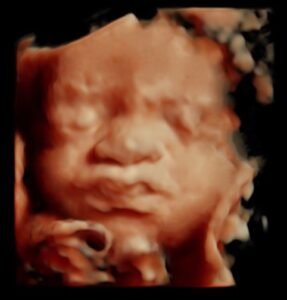

Notre Galerie.

Découvrez notre galerie vous présentant quelques photos inoubliables issus de nos dernières échographies 3D et 4D réalisées au sein de notre centre MonBébéEn4D !